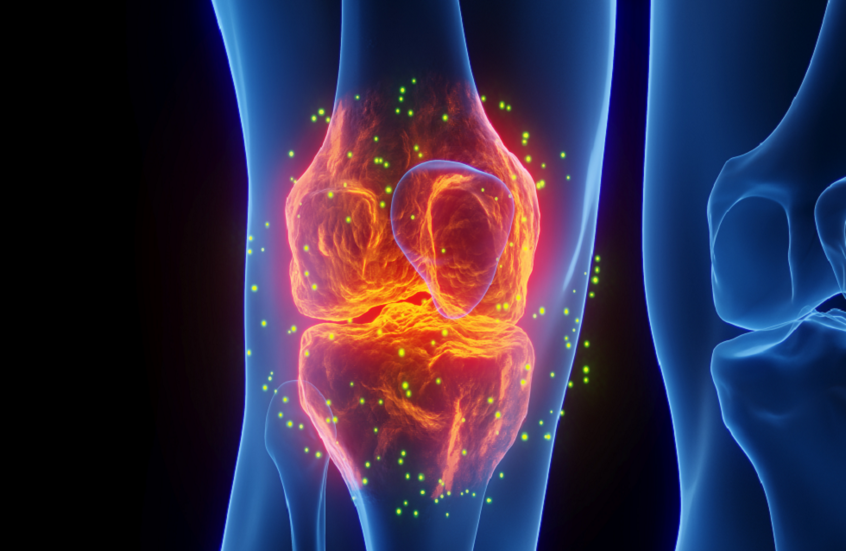

ابتكار جديد قد يحدث ثورة في ترميم العظام

ابتكر باحثو المعهد الفدرالي السويسري للتكنولوجيا في لوزان (EPFL ) مادة شبيهة بالعظام تساعد على ترميم العظام بسرعة وكفاءة أكبر.

واستلهم الباحثون هذه المادة من الخصائص الميكانيكية المرنة للعظام، وطوروا "حبرا" خاصا يمكن طباعته بتقنية ثلاثية الأبعاد أو حقنه ليصبح هياكل صلبة تشبه العظام الطبيعية. ويعتمد هذا الابتكار على استخدام إنزيمات طبيعية لتسريع عملية التمعدن في درجة حرارة الغرفة، ما يقلل استهلاك الطاقة مقارنة بالطرق التقليدية التي تحتاج إلى حرارة عالية.

ويعتمد الحبر المطوّر على أحد المكونات الأساسية للعظام، وهو معدن هيدروكسي أباتيت (HA)، ويمكّن الباحثين من إنتاج هياكل مسامية قوية وخفيفة الوزن خلال أيام قليلة. وبعد أربعة أيام من عملية التمعدن، يمكن لهذه الهياكل الصغيرة تحمل وزن الإنسان البالغ على مساحة لا تتجاوز 1.5 × 1.5 سنتيمتر.

وتقول إستر أمستاد، رئيسة مختبر المواد اللينة (SMaL) في EPFL: "فكرتنا كانت تطوير مادة قابلة للطباعة ثلاثية الأبعاد والحقن تتحول إلى هياكل ذات خصائص ميكانيكية مشابهة للعظام التربيقية عالية المسامية، مثل تلك الموجودة في فقرات الإنسان وعظام الفخذ".

ويعتمد الابتكار أيضا على إضافة جزيئات صغيرة من الجيلاتين الخالي من الإنزيمات، والتي تذوب تاركة مسامات داخل الهيكل. وهذه المسامات تتيح للخلايا الطبيعية التغلغل ونمو عظام جديدة عند زرع الهياكل في موضع الكسر، ويمكن التحكم في حجمها وكثافتها لضبط مسامية الهياكل حسب الحاجة.

وأظهرت التجارب أن إدخال مسامات تشكل نحو 50% من حجم الهيكل يخلق مساحة كافية لنمو الخلايا. وبعد 14 يوما من زرع الخلايا الجذعية البشرية، لاحظ الباحثون نمو الكولاجين وبروتين "أوستيوكالسين"، وهما مؤشرات على تكوين عظم جديد، ما يثبت إمكانية استخدام هذا النهج في تجديد العظام بشكل طبيعي.

وتشير أمستاد إلى أن الهياكل المنتجة بهذه الطريقة أقوى من تلك المصنّعة بطرق الحرارة العالية، وتتمتع بقوة ضغط تضاهي العظم التربيقي البشري. كما يمكن طباعة هياكل معقدة باستخدام هذه التقنية مع الطابعات الحيوية المتوفرة تجاريا.

وأضافت: "نتطلع إلى أن يفتح عملنا الطريق لتطوير هياكل قابلة للحقن تساعد على تجديد العظام".

نشرت الدراسة في مجلة Advanced Functional Materials.